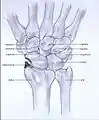

Stages

Post-traumatic osteoarthritis can be classified into four stages.[1][6] These stages are similar between SLAC and SNAC wrists. Each stage has a different treatment.

- Stage I: the osteoarthritis is only localized in the distal scaphoid and radial styloid.

- Stage II: the osteoarthritis is localized in the entire radioscaphoid joint.

- Stage III: the osteoarthritis is localized in the entire radioscaphoid joint with involvement of the capitolunate joint.

- Stage IV: the osteoarthritis is located in the entire radiocarpal joint and in the intercarpal joints. It also may involve the distal radio-ulnar joint (DRUJ).

Stage I

Stage II

Stage III

Stage IV